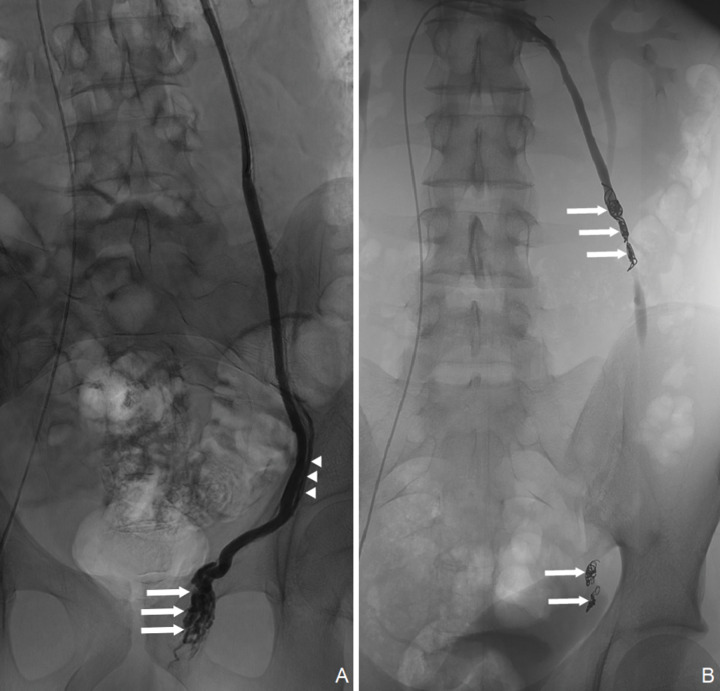

Background: Varicocele is a common condition in men that can lead to several clinical problems. Treatment modalities include surgical and non‑surgical methods. There has been no randomized controlled trial proving the superiority of one treatment approach over another. Materials and methods: We conducted an 8‑year retrospective analysis of varicocele embolization procedures at our department of Interventional Radiology. Demographic data, procedure details, procedure success and complications were collected. Telephone interviews were also conducted at the time of the study. Results: A total of 182 interventions were performed. Median age of patients at presentation was 31 years (range, 12-71). Median follow‑up duration was 44.5 months (range, 3.4-106.9). Employed embolic agents were coils in 171/182 (91.94%) cases. Technical success rate was 88.15%. Ultrasonographic success was accomplished in 44.87% patients. Clinical success rate in patients referred for scrotal pain was 70.42%. Fluoroscopy time was 20.3 ± 14.9 min (mean ± SD), dose area product was 63.2 ± 50.5 Gy∙cm² (mean ± SD) and kinetic energy released per unit mass was 193.2 ± 173.6 (mean ± SD). Minor complications were encountered in 19/182 (10.45%) of the interventions. Conclusions: Varicocele embolization was found to be an efficient and safe procedure for patients referred for scrotal pain. Randomized controlled trials are warranted to elaborate treatment algorithms in varicocele patients.